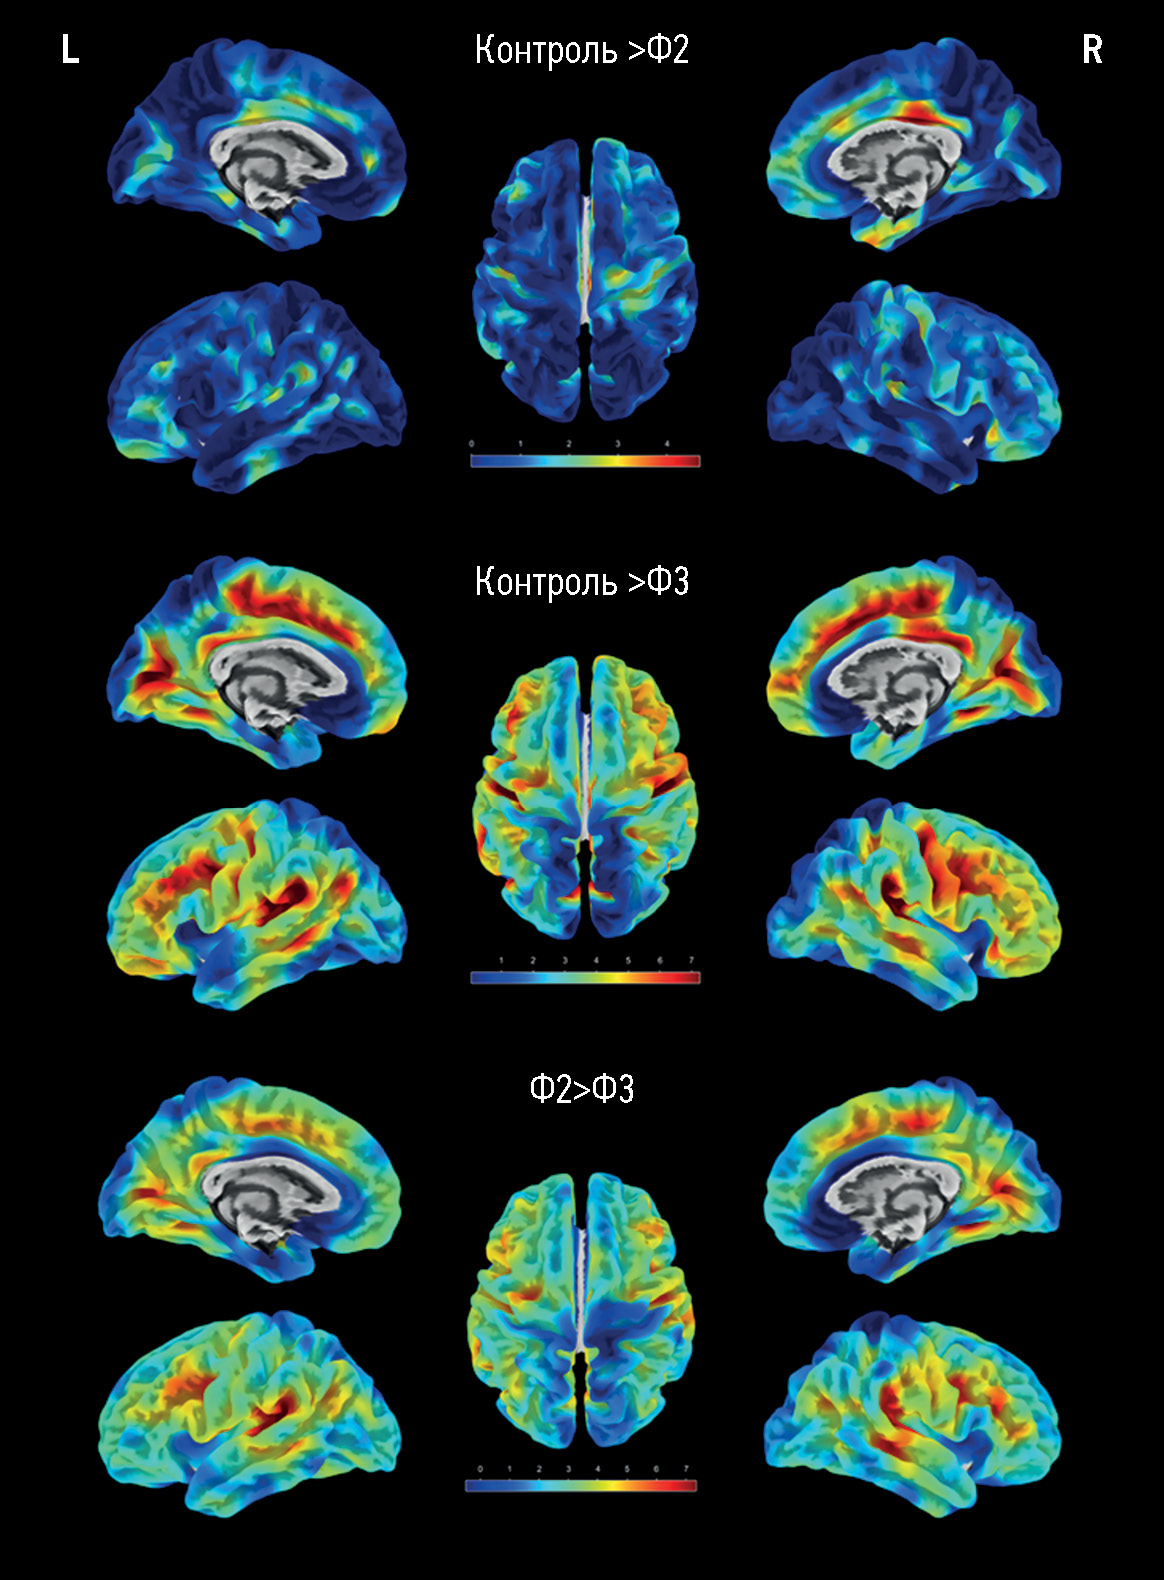

Surface-based morphometry of the cerebral cortex in cognitive impairments of varying severity in patients with age-related cerebral small vessel disease

Abstract

BACKGROUND: Analysis of structural magnetic resonance images is essential to assessing the main substrate of cognitive impairment in sporadic age-related cerebral small vessel disease, accounting for up to 45% of all dementia cases. Variations in the results of magnetic resonance morphometry applied in cerebral small vessel disease require extensive studies and clinical correlation.

AIM: To assess cerebral atrophy features in cognitive impairment in patients with cerebral small vessel disease by surface-based morphometry.

MATERIALS AND METHODS: A prospective study was conducted to assess patients with cerebral small vessel disease and cognitive impairments of varying severity levels (subjective, moderate, and dementia) and sex- and age-matched groups of volunteers. The assessment included the analysis of signs of cerebral small vessel disease based on the results of magnetic resonance imaging with the computation of general cerebral small vessel disease index and processing T1 multiplanar reconstruction images by surface-based morphometry to quantify general and regional brain parameters, including the thickness of the cerebral cortex.

RESULTS: The main group consisted of 173 patients with cerebral small vessel disease, whereas the control group included 47 healthy volunteers. As the severity of brain structural changes and cognitive impairments increased, a significant (p <0.05) decrease in the cortical thickness of certain regions following a similar pattern was reported, particularly in the cingulate gyri, mainly their posterior sections; medial and middle sections of the frontal lobes, various areas of the insular cortex, and temporoparietal areas, particularly the supramarginal gyri. The brain volumes (overall, gray matter, and white matter volumes) in cerebral small vessel disease were significantly different only in controls but not between patients with cognitive impairment of different severity levels. The hyperintense white matter volume was significantly different between patients with dementia and moderate cognitive impairment, dementia, and subjective cognitive impairment (p <0.0001).

CONCLUSIONS: The results confirm secondary/mixed atrophy in cerebral small vessel disease. The clarification of the severity level of cognitive impairment in cerebral small vessel disease based on atrophy data is limited by the wide variety of regions with significant cortical thinning. Thus, the quantification of the cortex can only be a supplementary method in predicting cerebral small vessel disease progression.

436-449